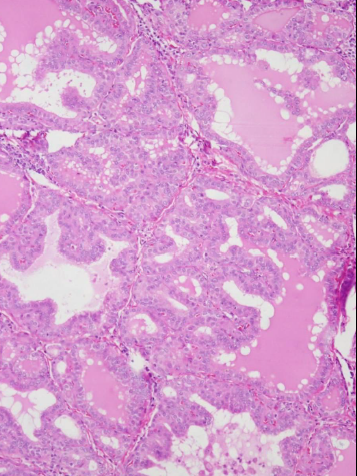

Graves’ Disease Histology

Irregular follicles and scalloped colloid